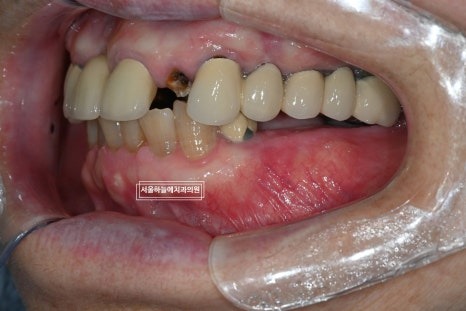

위아래 공간이 매우 부족한 상태였기 때문에

무리한 진행보다는

1차 수술만 먼저 진행하기로 하였고,

수술 후 약 1개월 반 정도 지난 뒤

아래 앞니 크라운 치료를 먼저 진행해 교합을 안정시킨 후

임플란트 2차 수술을 진행했습니다.